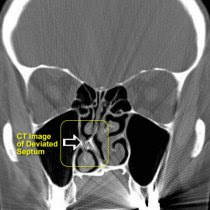

- tulang hidung bengkok (pada tulang tengah pemisah antara lubang hidung kiri dan kanan – istilah medis : septum deviasi) (gbr.4)

Gbr.3 | Gbr.4 |